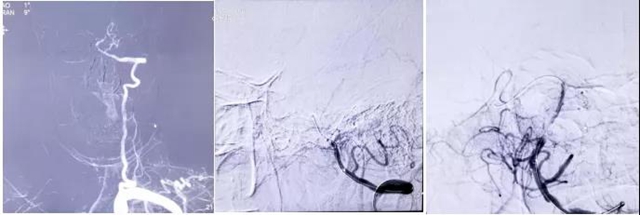

情况紧急,西南医科大学附属中医医院心脑病科副主任兼神经内科副主任刘天助博士接诊后,立即为刘婆婆开通了“脑卒中绿色通道”,紧急会诊,急诊进行头颅CT及术前造影。

结合基层医院CTP检查结果发现,刘婆婆后循环和左侧大脑半球灌注异常,梗死体积小于缺血区域1/3,基底动脉急性、左侧大脑中动脉M2段闭塞rtPA静脉溶栓未能开通,闭塞考虑为心源性栓塞可能。

考虑刘婆婆后循环脑梗死,全麻和右美托咪定镇静后副作用较大,刘天助和家属沟通后决定,在局麻下进行手术,尽量制动刘婆婆头部和肢体。

经过一个小时紧张的手术,刘天助分别从婆婆基底动脉和大脑中动脉取出两块质硬血栓,刘婆婆的脑血管完全恢复了通畅。